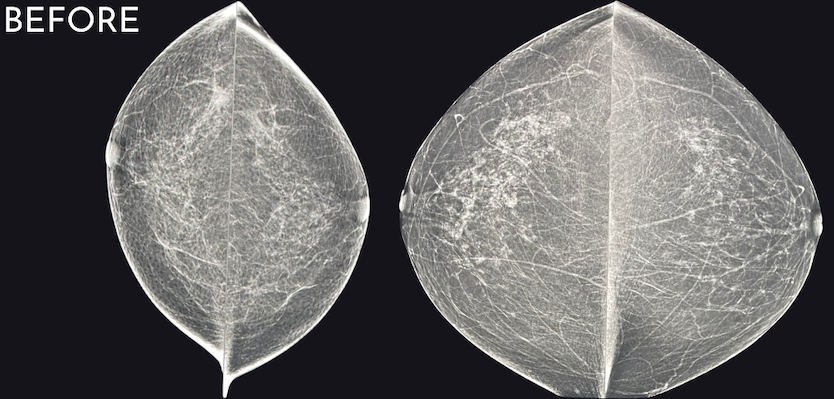

When comparing “before” and “after” images, the improvement can often be startling, even if the original images were really good! We have even identified cancers that were not visualized the year prior. Now that is amazing!